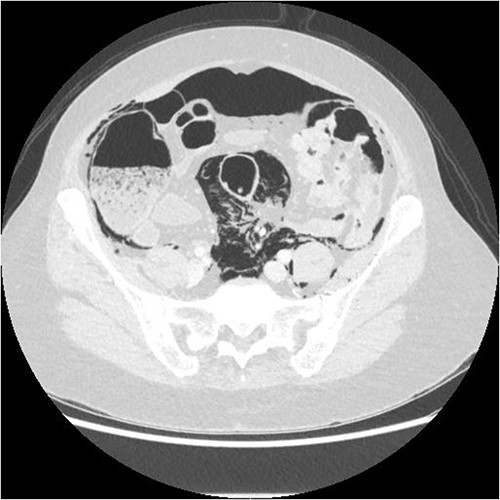

A chest X-ray confirmed subcutaneous emphysema and pneumoperitoneum and no pneumothorax (Fig. 1). Subsequent computed tomography (CT) of the abdomen and pelvis revealed extensive extraluminal gas throughout neck, torso and upper limbs including retroperitoneal, intraperitoneal, mediastinum, anterior and posterior chest wall, superficial and deep layers of the neck, right lower abdominal wall and bilateral inguinal canals (Figs 2 and 3).

Axial CT showing extensive intra- and extraperitoneal free gas.